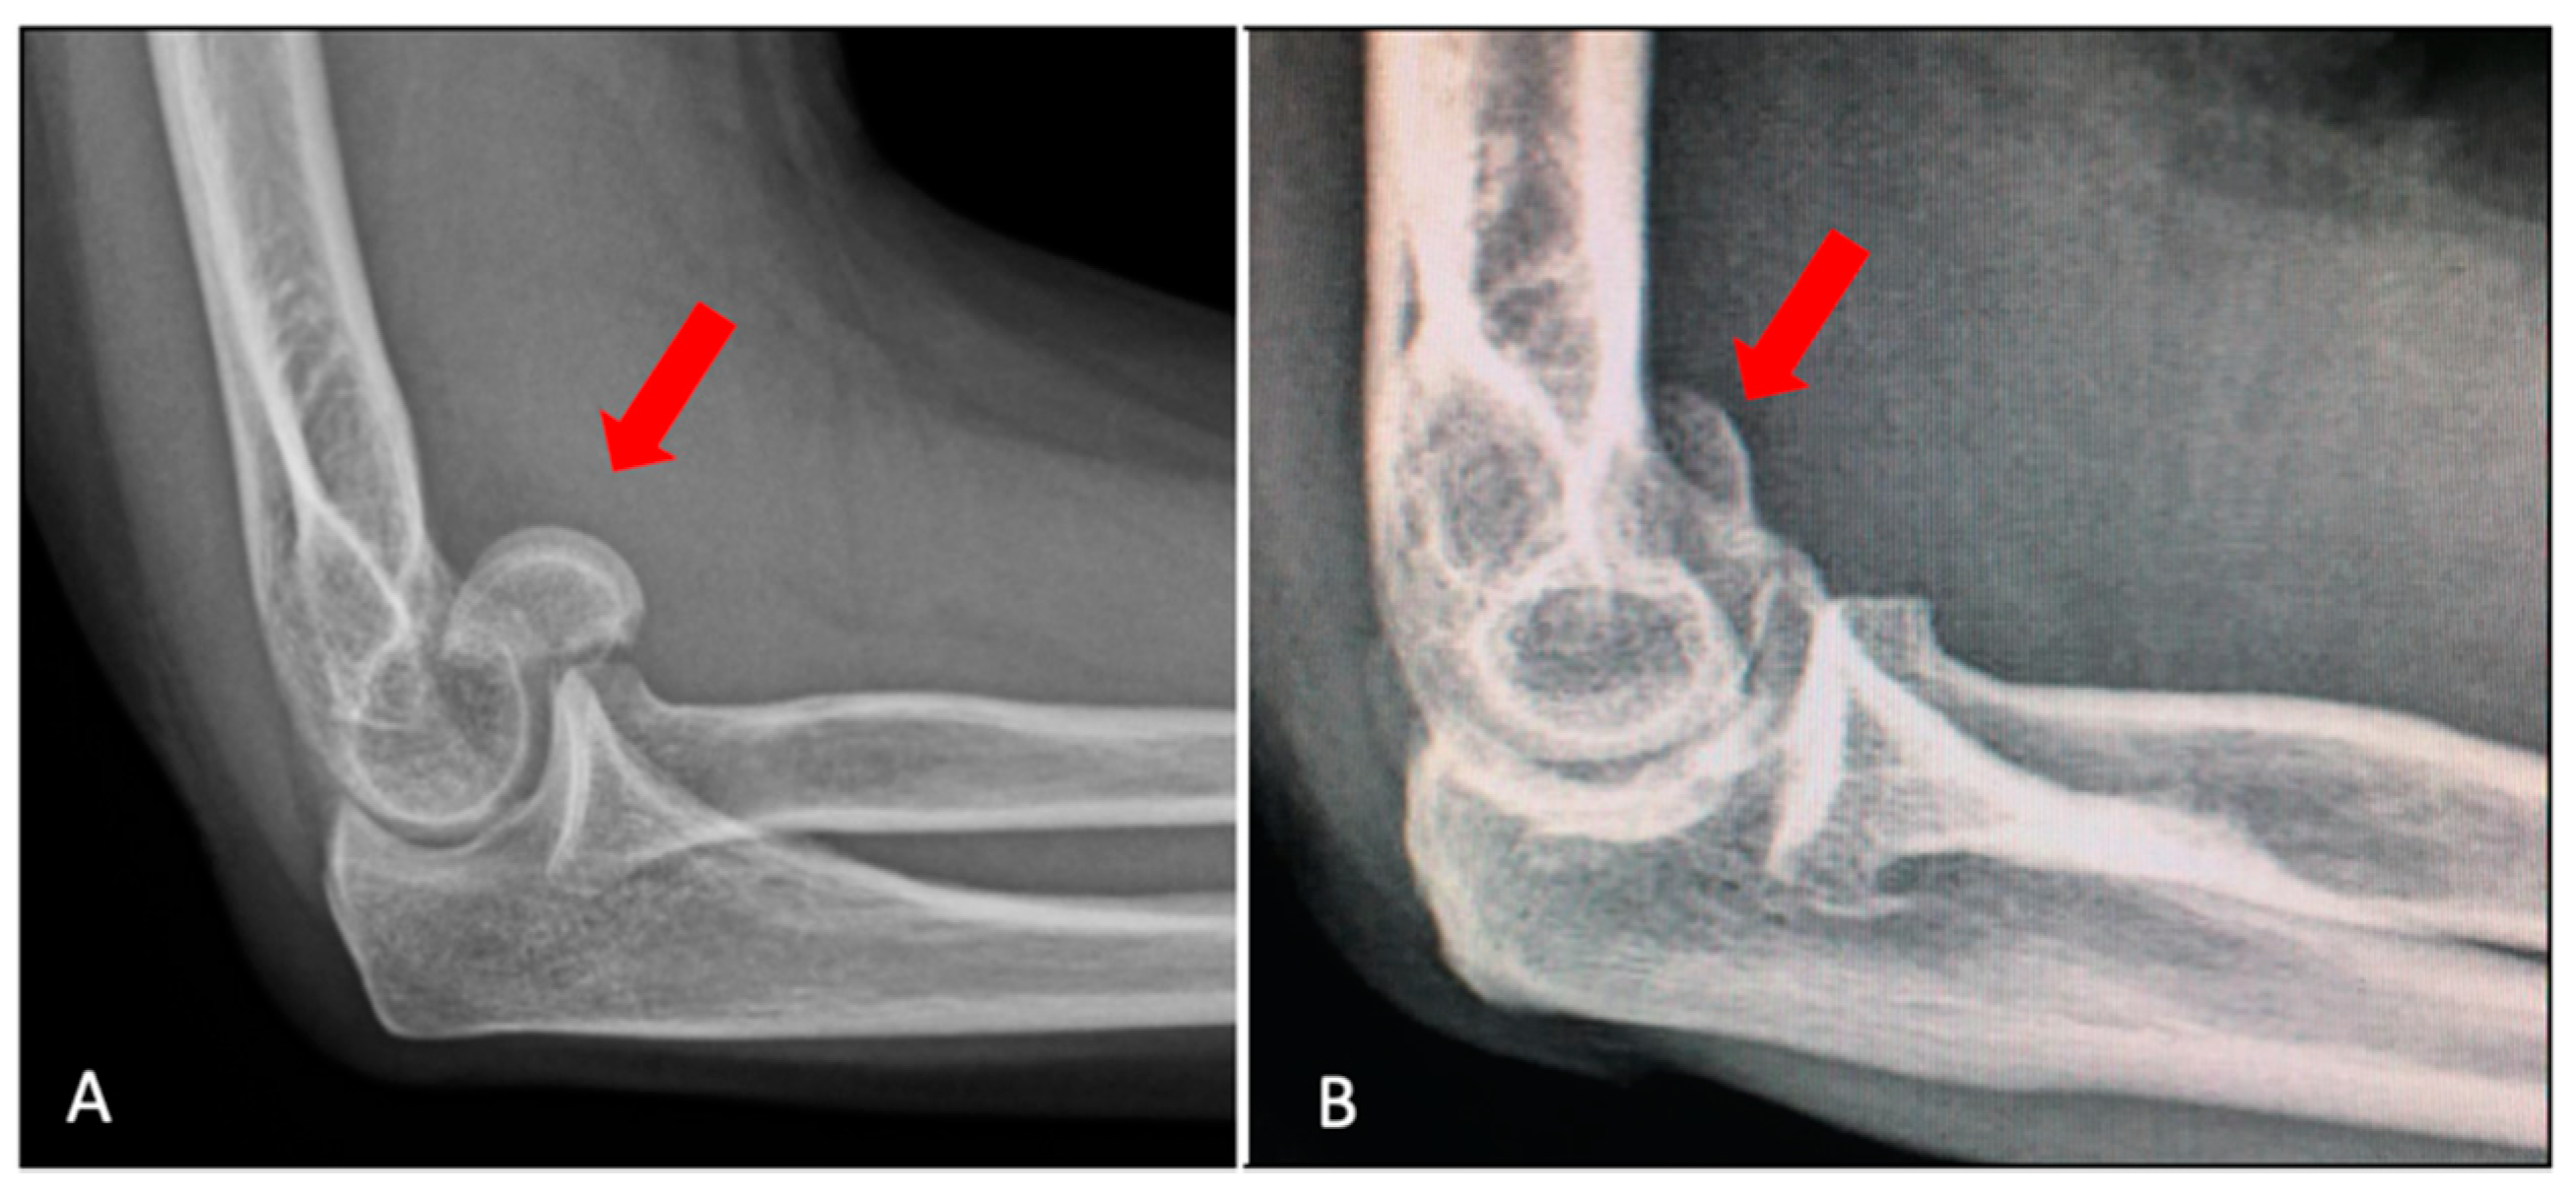

2. Classification

3. Imaging